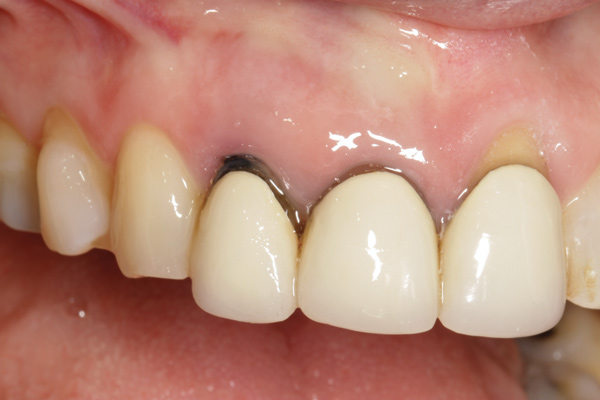

Fig 2. Radiograph showing implant was placed too deep and the diameter of the implant may be slightly larger than what was needed.

Figure 2

Caneva et al also suggested placing implants in a lingual (eg, cingulum) position to achieve optimal esthetic outcomes. The authors assessed the effect of implant positioning on resorptive patterns of the alveolar bone crest and demonstrated the importance of placing implants in a lingual position to minimize buccal bone resorption and thus prevent exposure of the implant. In their study, an average of 0.6 mm more buccal bone resorption was seen on implants that were placed in the center of the socket when healing after 4 months was compared histologically with implants that were positioned toward the lingual bony wall.17 In addition, placing a wider-diameter cylindrical implant in the extraction socket with the aim of filling the void between the implant and the inner socket wall was also shown to present greater buccal alveolar bone resorption (Figure 2).18,19 Based on these findings, it has been suggested that implant placement be performed in the palatal position of the socket to allow the formation of a gap between the implant surface and the inner buccal bone wall surface.19 More recently, in a retrospective cohort study, Cosyn and coworkers evaluated 115 patients who underwent implant placement with function. At 31 months, the buccal shoulder position of the implant was significantly associated with an increased likelihood of midfacial recession.3